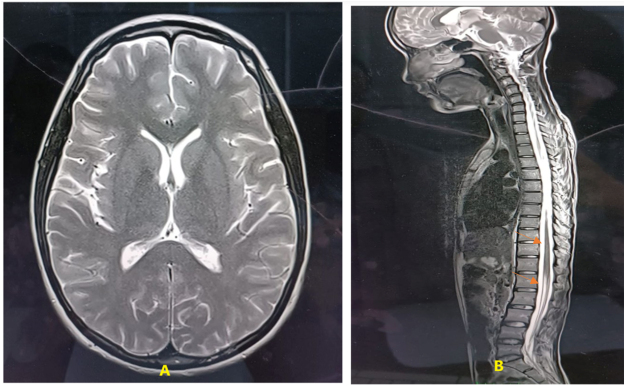

Case presentation: A 16-years-old female presented with long history of generalized weakness since age of 10 years, followed by bilateral sensorineural hearing loss, bulbar symptoms, and limb spasticity. Neurological examination revealed upper motor neuron signs in upper limbs, lower motor neuron signs in lower limbs, and bulbar involvement. Nerve conduction test was normal however, MRI showed early degenerative changes, and diagnosed with J-ALS after careful evaluation. She was started on Riluzole. Despite ICU care and supportive interventions including PEG and tracheostomy, she succumbed to respiratory failure.